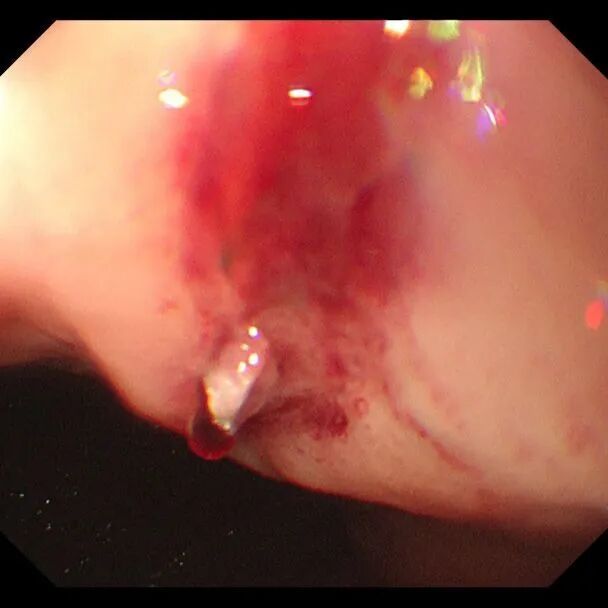

中午时分,在全麻状态下,消化内科团队为张师傅完成了急诊胃镜。检查发现,出血点位于食管-贲门连接处,确诊为贲门黏膜撕裂(Mallory-Weiss综合征)伴活动性出血。这种撕裂往往由剧烈呕吐或干呕引发,而张师傅长期大量饮酒导致的胃黏膜脆弱,正是此次大出血的“导火索”。

发现出血点